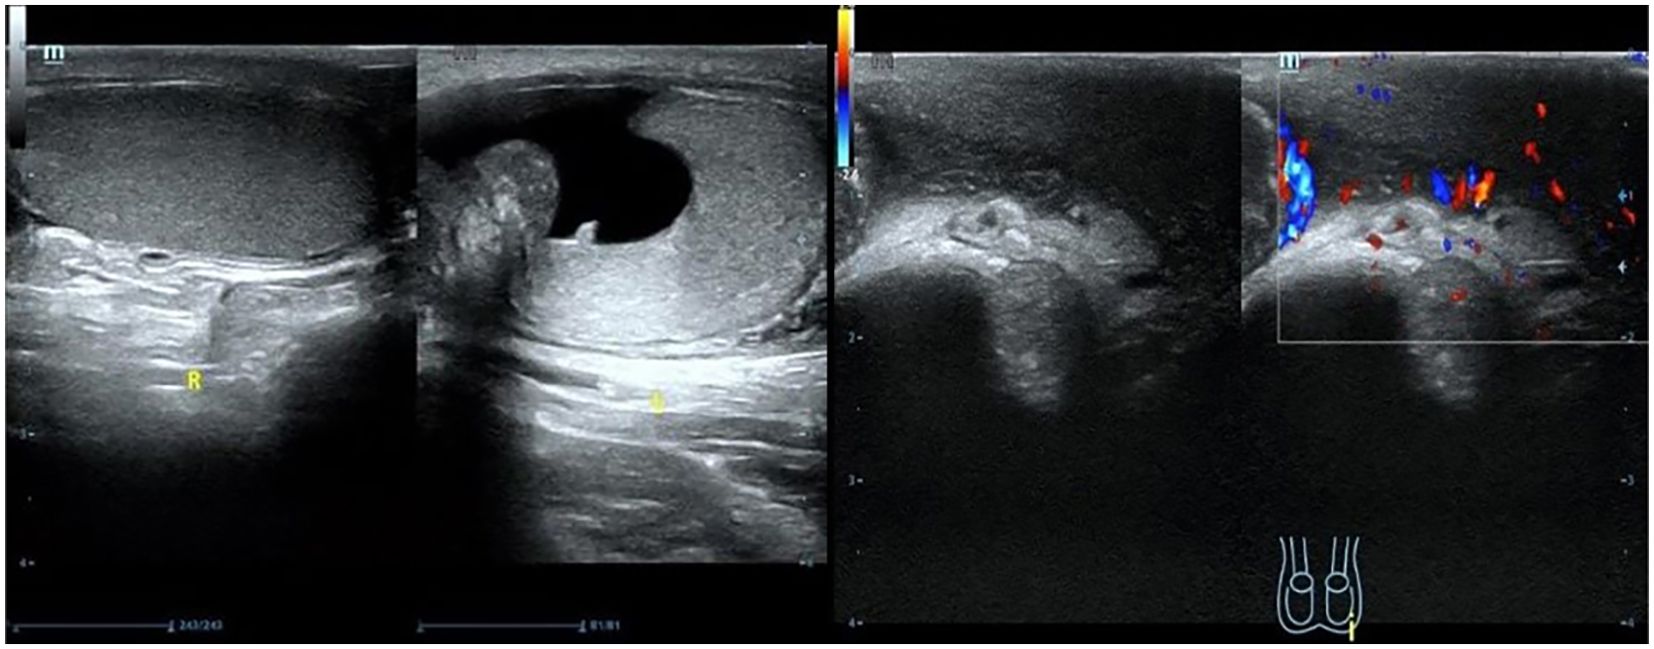

Scrotal ultrasound revealed that “the left testis was in the shape of ‘reverse C’, with abnormal morphology, the left epididymis had uneven echogenicity and rich blood supply, the left testis had an anterior liquid dark area, and the left spermatic cord was thickened, with uneven echogenicity and a slightly rich blood supply(Figure 1)”. The enhanced computed tomography (CT) scan revealed “cystic solid occupancy of the left testis: uneven density of the left testis, point-stripe enhancement in the parenchyma, showing a ‘fast-in-fast-out’ pattern, and no obvious enhancement in the cystic foci” (Figure 2).

Figure 1

The ultrasound demonstrates an inverted C-shaped left testis with abnormal morphology. The left epididymis shows heterogeneous echotexture and rich vascularity. A hydrocele is noted anteriorly. The left spermatic cord is thickened, heterogeneous, and hypervascular. The right testis is unremarkable.

Figure 1. Scrotal ultrasound.